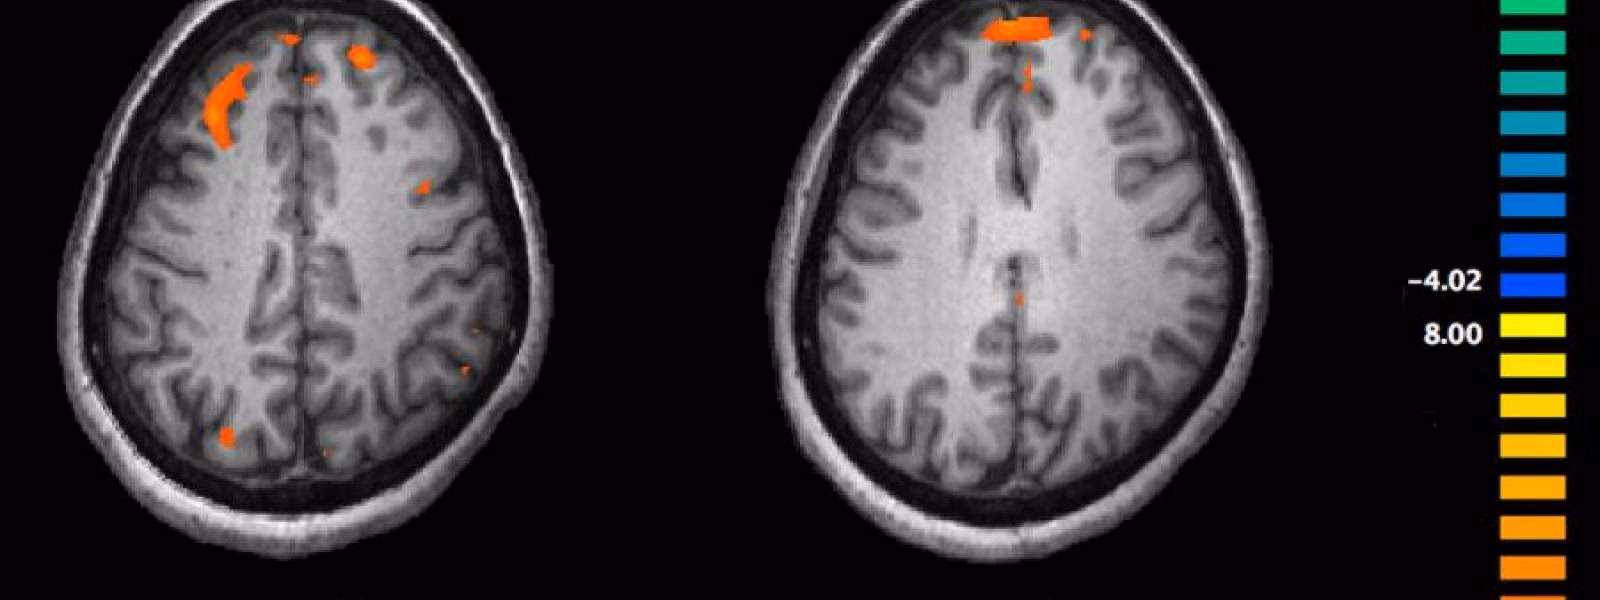

La estadística se aplica a nivel de vóxel (el equivalente tridimensional de un píxel en las imágenes de MRI). Se compara la señal de cada vóxel a lo largo del tiempo en las diferentes condiciones para identificar aquellos que muestran un cambio significativo y sincronizado con la tarea o estímulo. El resultado es un mapa estadístico paramétrico que muestra las regiones "activadas". Sin embargo, la interpretación estadística es compleja, especialmente debido a las múltiples comparaciones simultáneas (miles de vóxeles) y la presencia de ruido no relacionado con la tarea (movimiento del sujeto, respiración, pulsaciones cardíacas).

Durante un experimento, se adquieren secuencias de imágenes en diferentes condiciones experimentales. Dado que las imágenes individuales pueden variar debido al ruido y otros factores no relacionados con la tarea, los estudios de fMRI comparan conjuntos de imágenes adquiridas durante dos o más condiciones utilizando análisis estadísticos. Múltiples registros permiten promediar la señal y aumentar la fiabilidad de los resultados.

Este pequeño aumento de señal, típicamente alrededor del 1% o menos (aunque varía con la fuerza del campo magnético del escáner), es la señal BOLD registrada en fMRI. Cabe destacar que la respuesta hemodinámica (el cambio en el flujo sanguíneo y la oxigenación) es relativamente lenta. Después de un evento neuronal, hay un retraso de varios segundos antes de que ocurra la vasodilatación necesaria y el lavado de desoxihemoglobina. Por lo tanto, la señal BOLD es una medida indirecta y retrasada de la actividad neuronal subyacente.